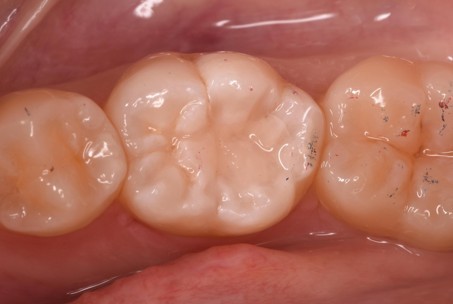

治療後 ![]() |

術後経過/現在の状態 |

欠けたり、痛みが出たりすることなく経過は良好です。 |